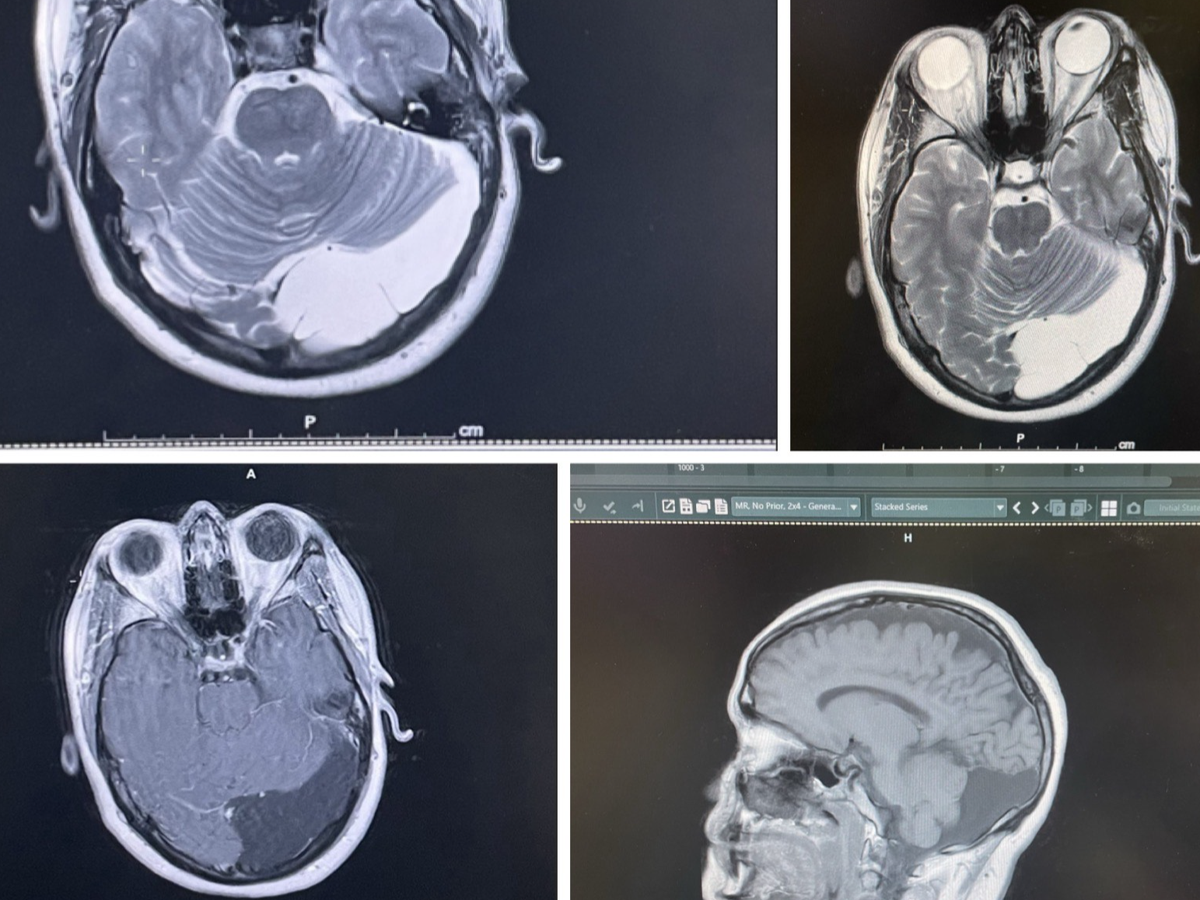

Earlier this year, I was at a friends house when I had a seizure and passed out. I was seated at the time, but still hit my head on the tile floor leaving a gash that needed stitches. The imaging done at the ER showed a 7.8 cm arachnoid cyst in the back of my skull compressing on my cerebellum, after following up with the neurosurgeon it was decided that given the size and new onset of symptoms surgery needs to happen.

Surgery will require a craniotomy (removal of a part of my skull and subsequent replacement with a titanium plate and screws) to access the cyst. I've been advised that the surgery is as low risk as brain surgery can be because it is thankfully just on the surface of my brain. I will be hospitalized for at least 3 days and then recovery is expected to take up to 6 weeks, which includes restrictions on driving.